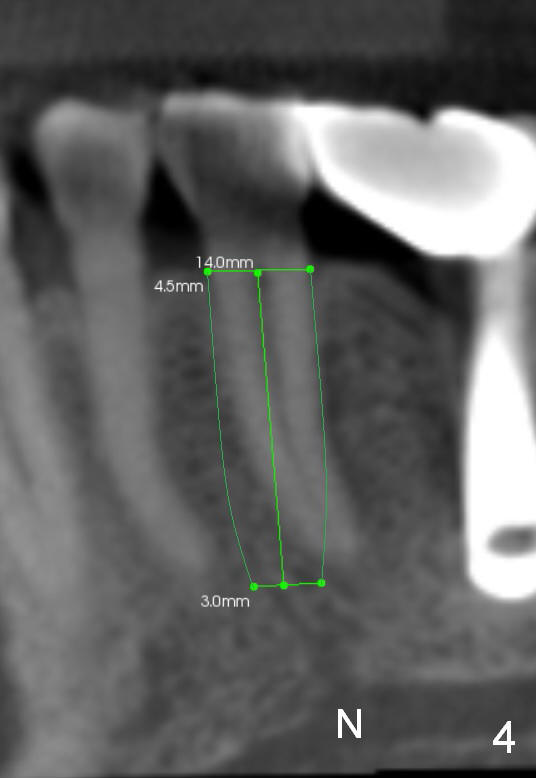

CT sagittal section of a similar case shows that the root is also long, but curved (Fig.4). A 4.5x14 mm implant is slightly longer than the root. The apex of the implant has distance to the underlying nerve (N). The coronal section shows that the implant should be placed lingually (Fig.5 L), since the buccal (B) plate is thin (Fig.6 between arrowheads). The first drill (2 mm) is to be placed lingually (Fig.7 red arrow). When the implant is placed, there should be a buccal gap, to be filled with bone graft (Fig.5 red circles).